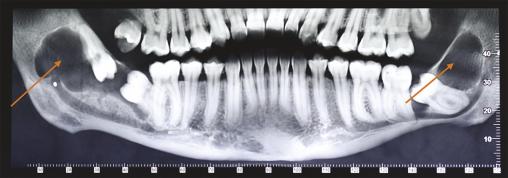

Cette femme de 26 ans consultait pour des douleurs récidivantes au niveau des dents de sagesse. Elle avait comme antécédents un asthme et une néphrectomie du rein droit en raison d’une dysplasie. Sa consommation tabagique était estimée à 6 paquets-année. Le panoramique dentaire (fig. 1 ) montrait quatre images radioclaires entourant les dents de sagesse. La patiente était alors adressée dans le service de chirurgie où un Cone Beam (fig. 2 et 3 ) permettait d’évaluer la taille des lésions kystiques ainsi que leurs rapports avec les structures anatomiques voisines. L’avulsion des dents de sagesse et l’énucléation des kystes étaient réalisées. L’examen anatomopathologique des lésions notait une paroi kystique bordée par un épithélium malpighien ortho- ou parakératosique avec une hyperplasie des couches basales compatible avec des kératokystes bénins odontogènes.